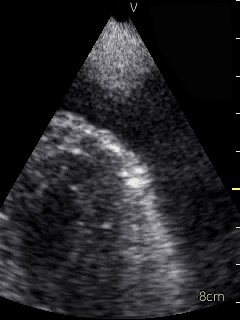

Video 1 (online supplement; Figure 1) demonstrates a parasternal long axis view with the pericardial effusion noted to be posterior to the left ventricle in this view. Video 2 (online supplement; Figure 2) is a short axis view of the heart which is showing that the effusion is surrounding the heart. Video 3 and 4 (online supplements; Figures 3 & 4) demonstrates that the pericardial effusion is present significantly surrounding the apex as well. An echocardiogram confirmed the POCUS findings and cardiology was consulted to conduct a pericardiocentesis, following which the patient’s symptoms resolved. The effusion was thought to be chronic and transudative. In this case, the use of POCUS at the bedside allowed for rapid detection of a large pericardial effusion and subsequent treatment.